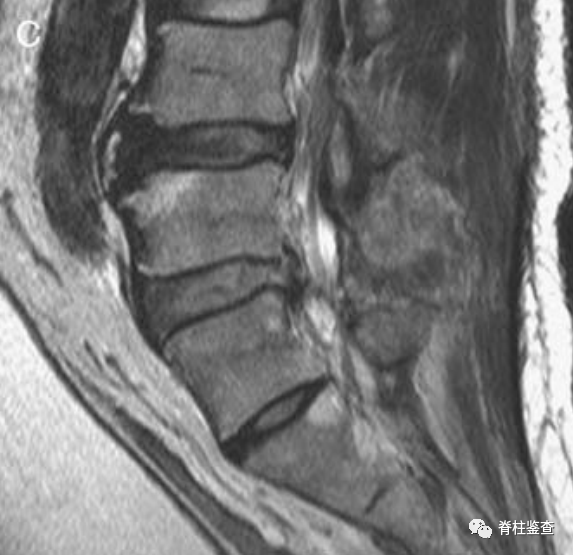

术后第1天显示,椎间盘充分移除;MR图像中的瘢痕组织限制了硬膜囊的充分扩张(白色↓)。